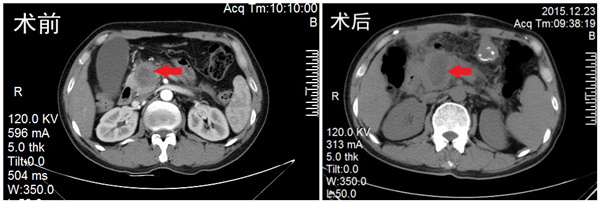

患者高某,男,48岁,以“皮肤、巩膜黄染2周”入院,彩超及CT提示胰头部实性占位并肝内外胆管、主胰管扩张。血清肿瘤标记物CA19-9升高。

在进行术前对两名患者做CT引导下经皮肝穿刺胆汁外引流手术(PTCD),在肝功能得到改善后,进行开腹纳米刀消融手术。首先麻醉成功后,手术开始进行,术中超声精准测量肿瘤大小及形状,将数据输入纳米刀治疗系统,进行布针设计并优化后,在术中超声引导下将纳米刀治疗电极按预定的设计方案穿刺入肿瘤进行消融治疗。消融后,实施胆管空肠吻合解除胆道梗阻,胃空肠吻合预防消化道梗阻。手术非常成功,截止目前,2例患者均恢复顺利,未出现手术期并发症。